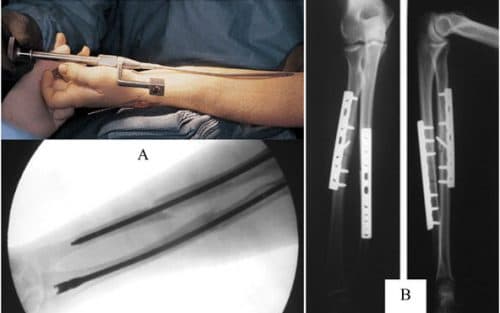

Gãy Xương Cẳng Tay Điều Trị Trong Bao Lâu & Cách Chăm Sóc

Xin chào chuyên mục tư vấn Cơ Xương Khớp! Tôi muốn nhờ chuyên mục tư vấn giúp tôi ” gãy xương cẳng tay điều trị trong bao lâu thì lành”? Em trai tôi bị gãy xương cẳng tay do đá bóng. Em tôi mới phẫu thuật và bó bột được 2 ngày. Tôi và gia […]